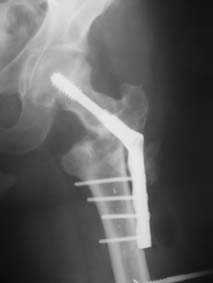

Возможно, пример (в приложении) поможет Вам определиться с выбором тактики лечения (у нашего пациента, кроме тугого ложного сустава вертельной области, сложная деформация н/3 бедренной кости; т.к. это не имеет значения к обсуждаемой теме - оставил "за кадром"). Как Вы видите, мы в данном случае не вводили чрескостные элементы в зону установки имплантата. При отказе от наложения опоры на таз (кстати, она не обязательно может быть громоздкая спицевая; арки со стержнями-шурупами, введенными в крыло подвздошной вполне достаточно) "не удивляйтесь", если опора со стержнями-шурупами, введенными в вертельной области в скором времени дестабилизируется, возникнет воспаление мягких тканей у чрескостных элементов. Такая опора "имеет на это право": нагрузка конечности от вершины дистального фрагмента до кончиков пальцев ляжет на нее. А двух-трех введенных рядом стержней-шурупов, как их не разноси от фронтальной плоскости, в данном

случае явно недостаточно для адекватной фиксации. + для того, чтобы выбрать оптимальные чрескостные элементы для промежуточной и дистальной опор, можете воспользоваться атласом